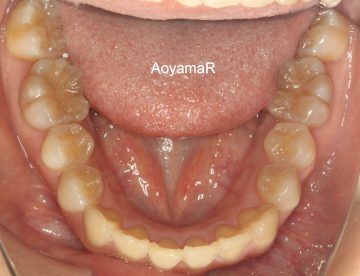

過蓋咬合(かみ合わせが深い、オーバーバイト)の矯正症例

CASE 15

(20歳 女性 )

マウスピース型カスタムメイド矯正装置(インビザライン)単独による治療

治療前